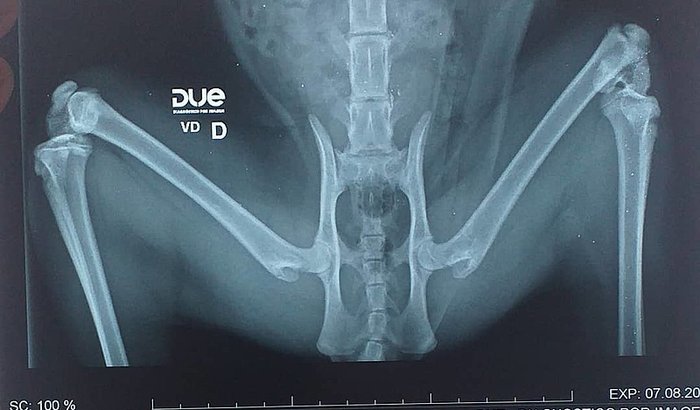

Plutao É meu gato, ele tem 9 meses, ontem descobrimos que ele quebrou o femo. Corre pra lá, corre pra ka, fomos atrás de várias possibilidades tentando encontrar uma forma viável de realizar a cirurgia. Infelizmente não existe um sistema único e público de saúde para animais, teremos de pagar 1200 reais pra que o plutao possa realizar essa operação. Sem condições de arcar com a cirurgia resolvi fazer uma vaquinha online. Me ajudem contribuindo ou compartilhando, pra que o plutao possa realizar logo sua cirurgia. Gratidão 🍀🙏🏽